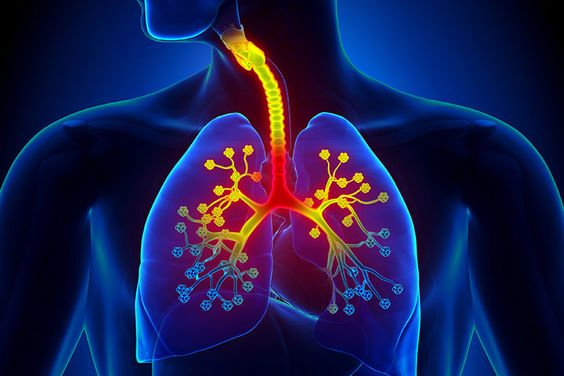

안녕하세요! 오늘은 ‘폐렴’의 증상에 대해 자세히 알려드릴게요

요즘처럼 일교차가 크고 면역력이 떨어지기 쉬운 계절에는

감기나 독감 뒤에 폐렴으로 악화되는 경우도 많습니다.

특히 노약자, 만성질환자, 어린아이에게는 치명적일 수 있죠.오늘은 초기에 알아두면 생명을 지킬 수도 있는

폐렴의 주요 증상 10가지를 아주 상세히 알려드릴게요.